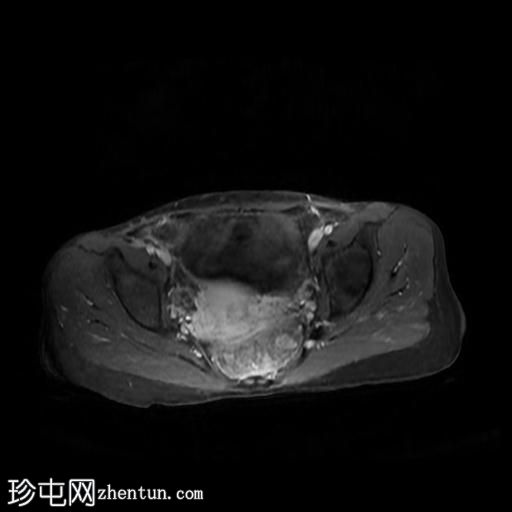

冠状位T2加权像

脂肪抑制

轴位

T2加权像

轴位T1加权像

增强脂肪抑制

冠状位T1加权像

回肠末端及盆腔回肠肠袢可见长段肠壁增厚及强化,肠周血管丰富,呈“梳状征”,并可见明显的纤维脂肪浸润。

未见瘘管、积液、腹水或梗阻。

磁共振肠道造影(MRE)结果支持克罗恩病的诊断,显示远端及末端回肠以活动

性病

变为主,并可见明显的肠周血管。